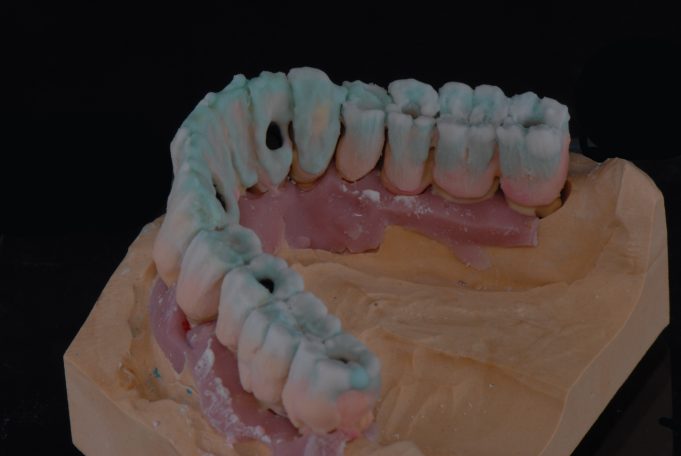

Verschraubte Implantatbrücken fühlen sich für den Patienten an wie die eigenen Zähne.

Implantsteg verankerte Brücke. Für den Patienten abnehmbar, aber der Tragekomfort von festen Zähnen.